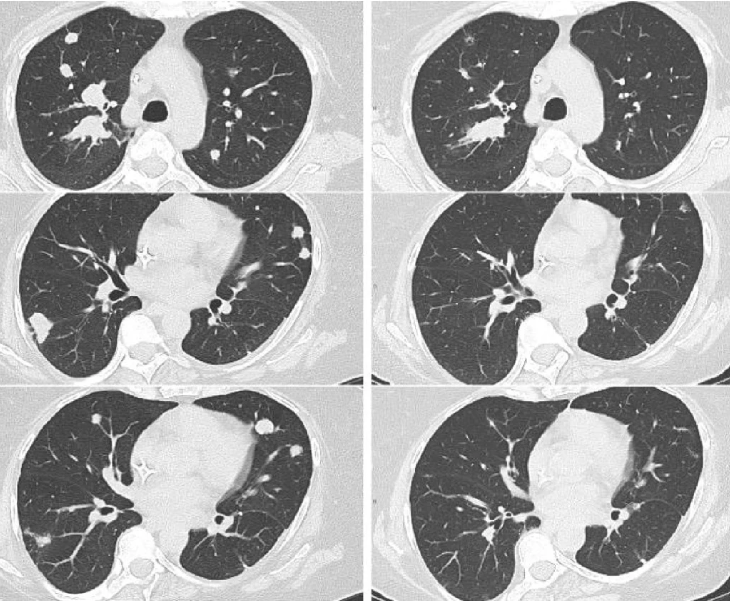

在过去的几年中,细胞免疫疗法为癌症治疗提供了一种新的策略。最近的临床研究表明,肿瘤浸润淋巴细胞(TIL)治疗在晚期实体瘤的治疗中显示出良好的疗效,这为癌症患者带来了新的希望。

近年来,癌症治疗领域迎来了一场革命性的变化。从传统的手术、化疗和放疗到靶向治疗和免疫治疗,科学技术的进步不断重塑着癌症治疗的模式。其中,细胞免疫治疗作为有前途的方向之一,受到越来越多的关注。在各种细胞免疫疗法中,肿瘤浸润淋巴细胞(TIL)疗法近年来尤为突出,甚至在一些晚期癌症患者中取得了惊人的“临床治愈”效果。

在过去的几年时间里,细胞免疫疗法已经逐步成为了癌症治疗的有力策略。其中,肿瘤浸润淋巴细胞(TIL)疗法在实体瘤治疗中的临床应用显示出良好的疗效。